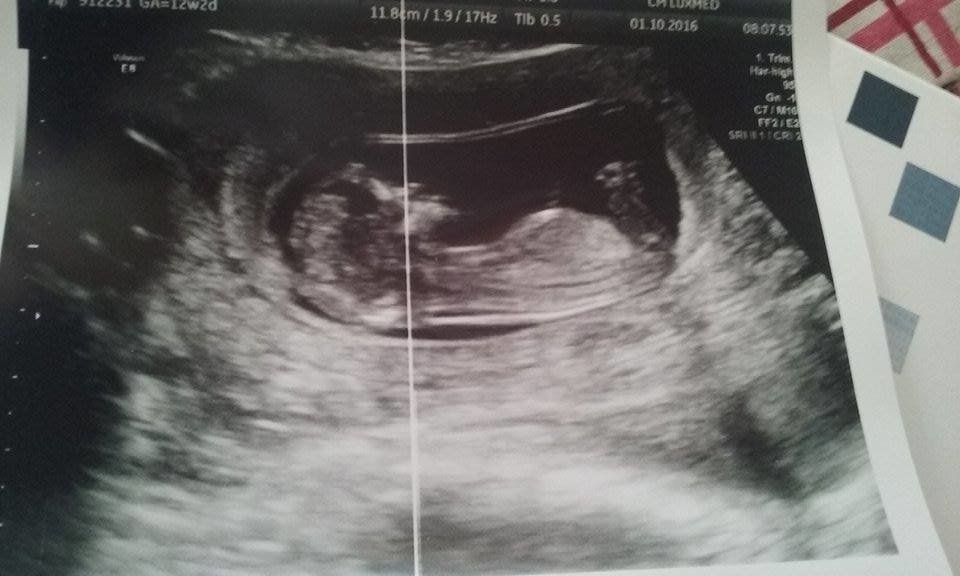

Nasza testy, usg, wizyty :-)

Zobacz załącznik 775911 Zobacz załącznik 775910

moje 6,02 cm szczęścia :) na pierwszej foteczce macha do Was rączką bo poprosiłam żeby sie przywitał z forumowymi cioteczkami :)

słodkie i wzruszające było widzieć jak sie porusza <3